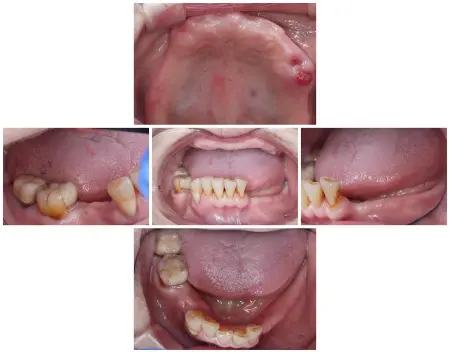

拝見したところ、上下ともに取り外し式の部分入れ歯が装着されていましたが、下顎には状態が悪く温存できない歯が3本あり、噛み合わせの高さがずれる「フレアアウト」も見られました。

フレアアウトは、歯ぐきや歯を支える骨が細菌感染する「歯周病」をはじめとするいくつかの原因が重なって歯並びや噛み合わせが崩れることで生じ、出っ歯やすきっ歯など噛み合わせが悪くなるリスクがあります。

患者様の場合もフレアアウトを放置した結果、上顎のフルジルコニアブリッジが前方に突出し、上下の部分入れ歯も外れやすくなり、しっかり噛むことが難しくなったと考えられました。

上顎はフルジルコニアブリッジ部分が前方に出ており、このままだと噛み合わせを整えることが難しいため、ブリッジを外して総入れ歯にする治療の必要性を説明しました。

前歯は歯の根を残すことも可能ですが、総入れ歯を顎の粘膜にしっかり吸着させるためにはすべて抜歯する必要があることもお伝えしたところ、治療に同意いただきました。

また下顎は温存できない歯3本を抜いてから、部分入れ歯を新しく作製します。